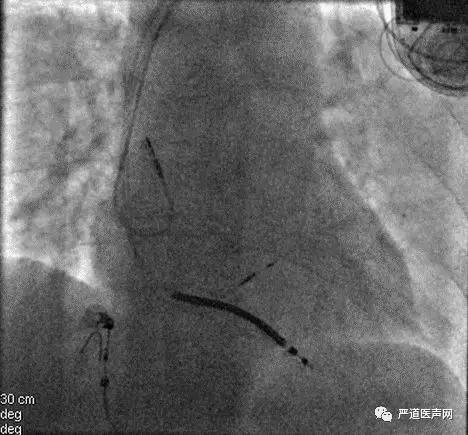

术后影像

因病人靶静脉成角畸形,电极进入十分困难,即便使用了鞘中鞘技术,也未成功,病人又频发室速,为了尽快缩短手术时间,顾翔教授当机立断,将手术方案进行调整,准备植入3830导线,将导线植入在病人的左束支区域,进行起搏,这种手术方法也是当下最先进的生理性起搏疗法,随即鲍正宇主任、陈福坤博士开始进行手术准备。在团队的努力下,很快导线植入完成,将术前154ms的QRS波缩短到112ms,测得导线参数:阈值0.5v/0.4ms,感知12mv,阻抗653Ω,手术十分成功,学员们也纷纷给顾翔教授团队点赞。

术后4天的超声心动图显示EF值已恢复到57%,并且病人已经顺利出院。